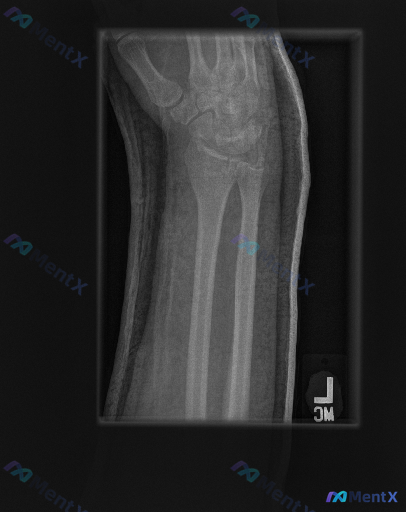

整理到一份左前臂及腕部侧位X光片的影像资料,先和大家同步客观所见的线索: 1. 骨骼方面:桡骨远端背侧和掌侧皮质有连续性中断,可见骨折线涉及关节面,断端有背侧移位、背侧成角的表现,局部有粉碎或压缩改变;尺骨远端(尺骨茎突)处也可见透亮线。 2. 关节方面:桡腕关节的对应关系有改变,随桡骨移位出现背侧...

【病例资料】 影像资料:左侧前臂侧位X光片 临床背景:成人,考虑创伤相关表现 从这张图像中可以注意到一些与正常情况不符的征象,包括骨皮质改变、关节对位、周围软组织等方面的异常。 想先听听大家的第一判断倾向——单看这张侧位片的表现,你更倾向于首先考虑哪类核心异常?